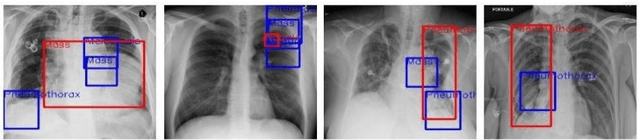

Advancements in Telemedicine as an approach to healthcare delivery have heralded a new dawn in modern Medicine. Its fast-paced development in our contemporary society is credence to the advances in Artificial Intelligence and Information Technology. This paper carries out a descriptive study to broadly explore AI's implementations in healthcare delivery with a more holistic view of the usability of various Telemedical Innovations in enhancing Virtual Diagnostic Solutions (VDS). This research further explores notable developments in Deep Learning model optimizations for Virtual Diagnostic Solutions. A further research review on the prospects of Virtual Diagnostic Solutions (VDS) and foreseeable challenges was also highlighted. Conclusively, this research gives a general overview of Artificial Intelligence in Telemedicine with a central focus on Deep Learning-based approaches to Virtual Diagnostic Solutions.